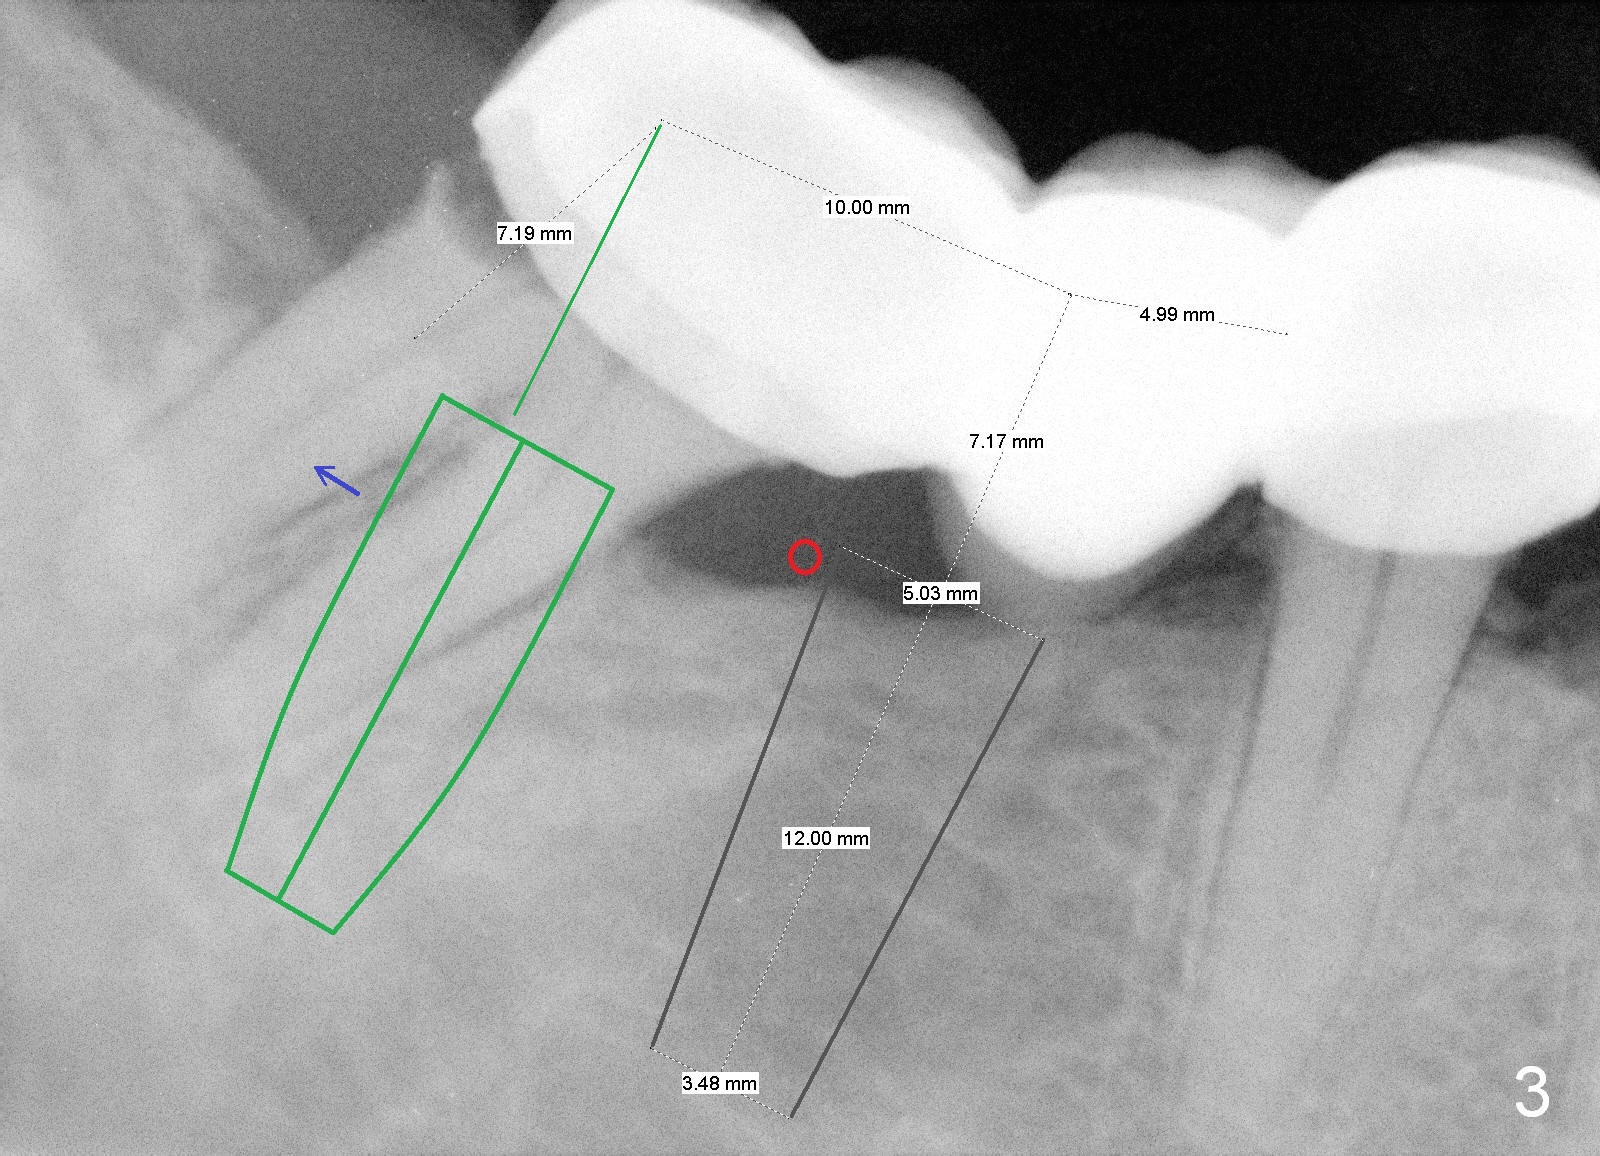

A 43-year-old man has a failed bridge (Fig.1: #29-31). The mesiodistal width of the pontic (#30) is pathologically narrow. When an implant is placed at the site, the osteotomy position should be moved distally, 5 mm from the distal surface of the tooth #29 (Fig.3), while the center of the osteotomy at the site of #31 should be 10 mm from the center of the osteotomy at the 1st molar.